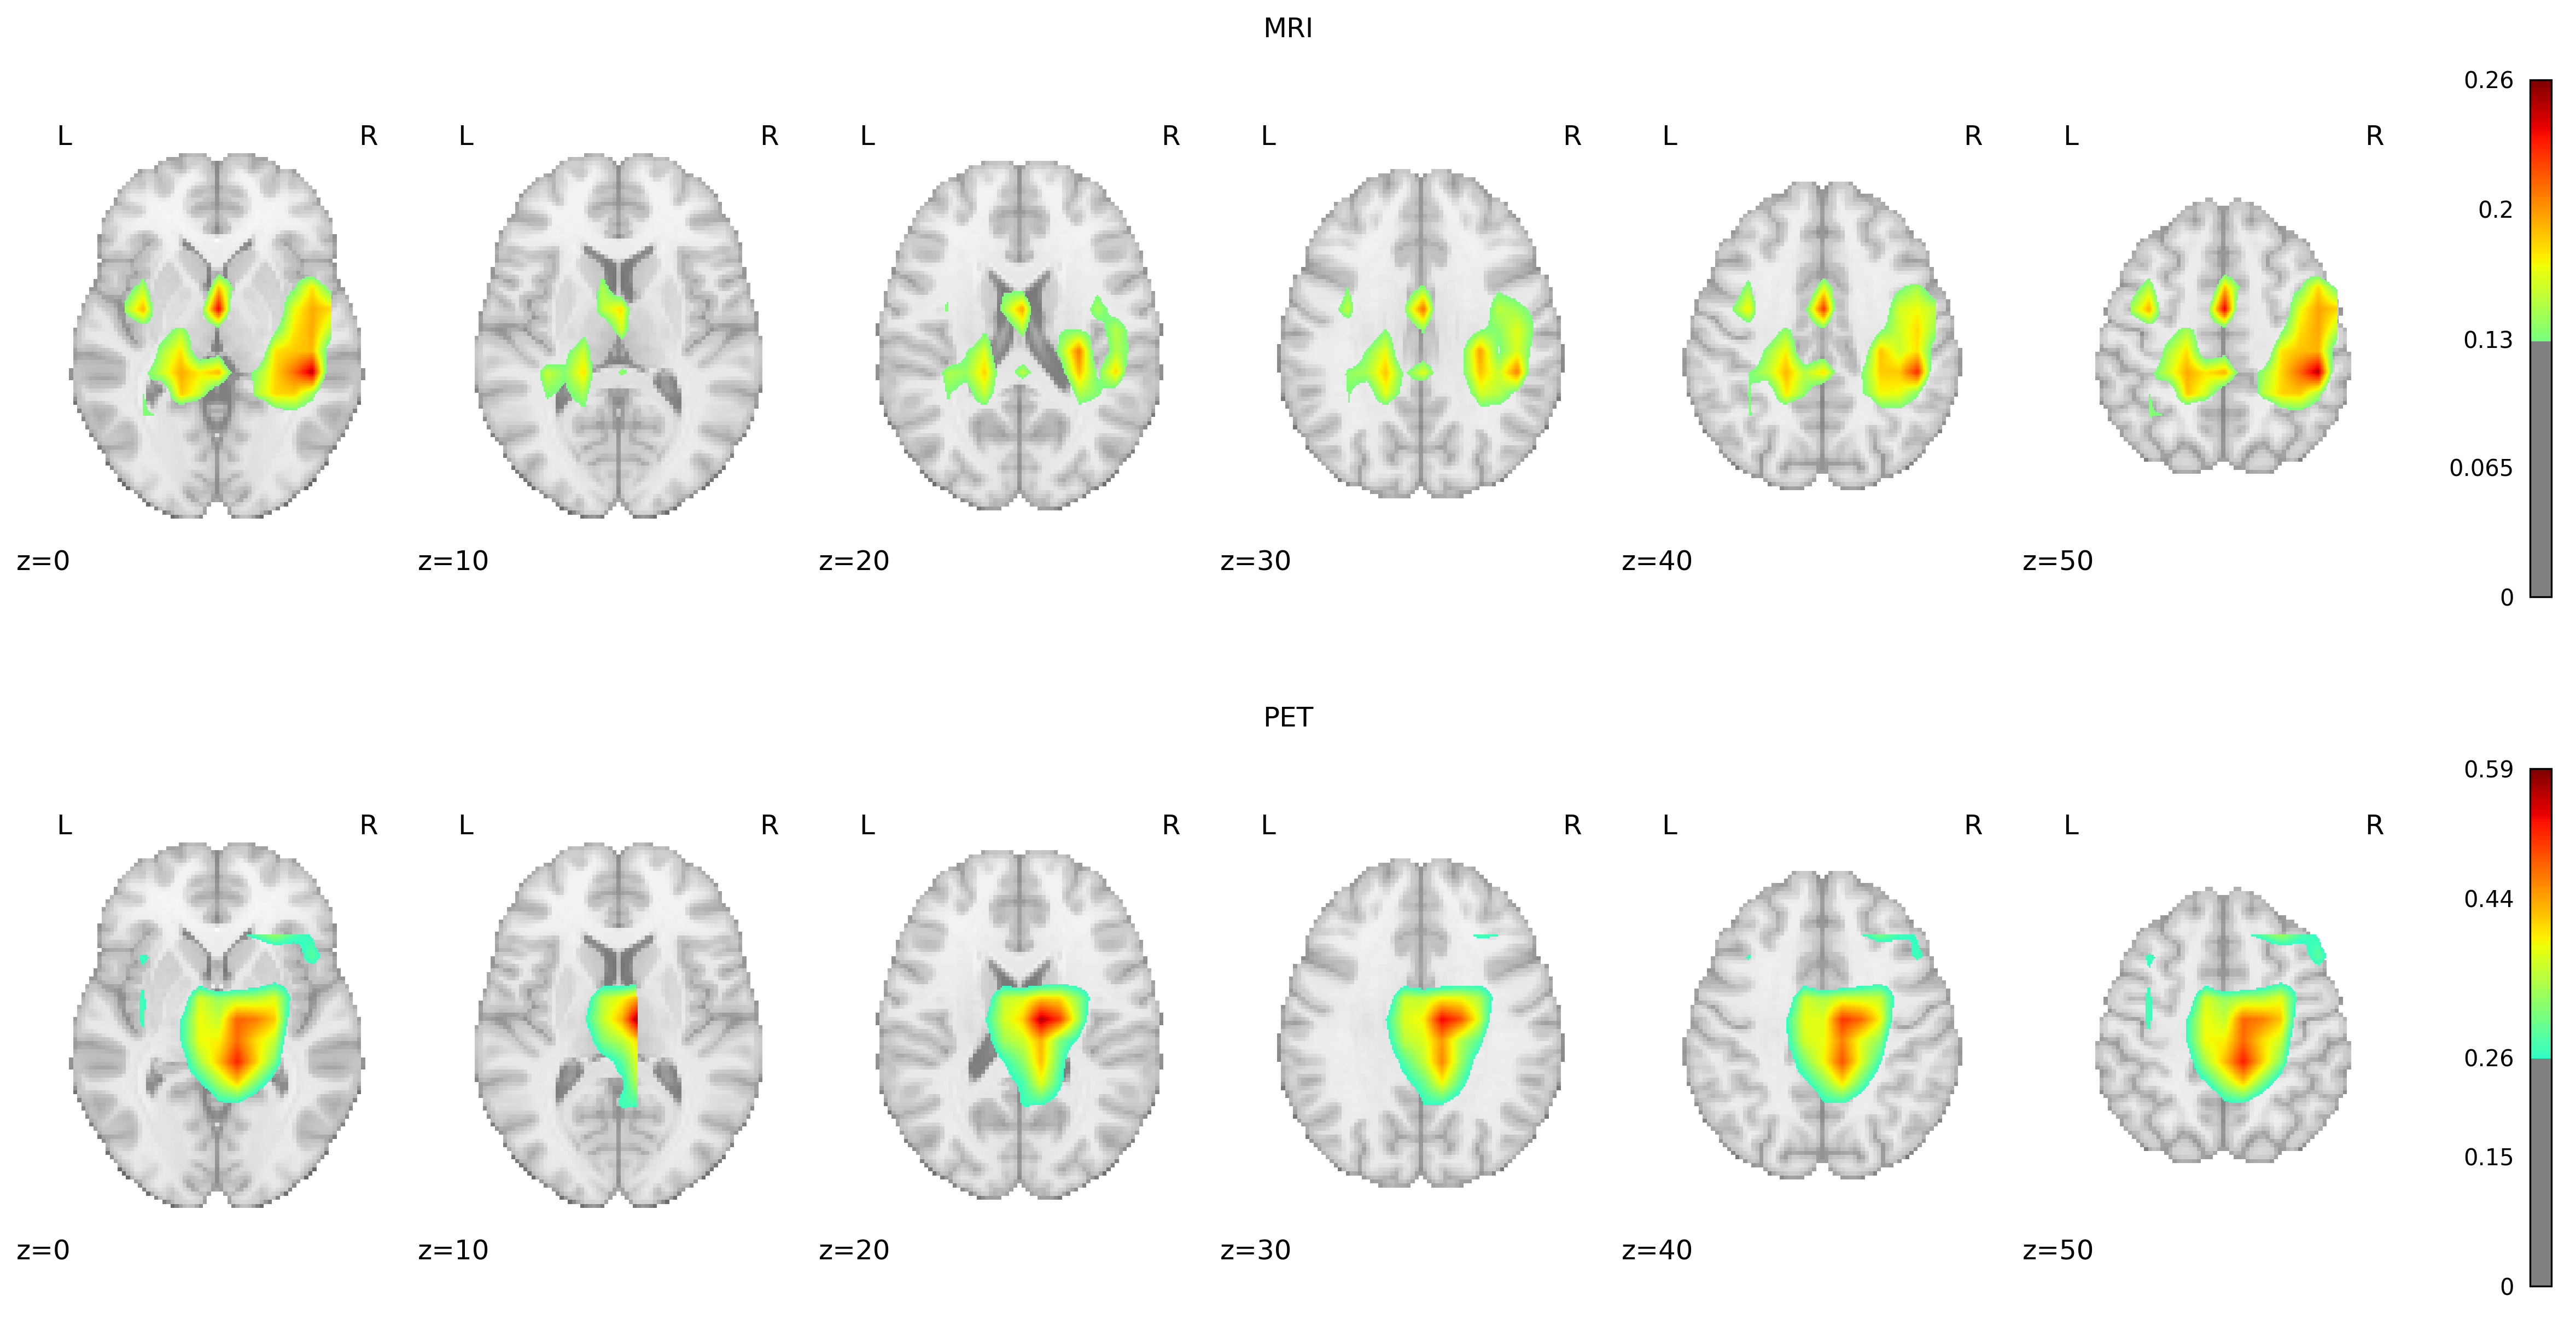

Overlaying Grad-CAM heatmaps onto the AAL2 atlas, a detailed anatomical guide encompassing 120 brain regions, allowed us to precisely identify the key areas influencing the model’s classifications. Identifying regions with mean Grad-CAM values in the top 90th percentile revealed their critical role in the model’s decision-making process, emphasizing their potential relevance to Alzheimer’s disease pathology.

Heatmaps for both MRIs and PET scans

Three-dimensional visualizations created from multiple axial brain slices, showcasing Grad-CAM heatmaps for the positive class.

For MRI scans, a notable consistency exists in the regions highlighted across both groups, with the Temporal Lobe emerging as the most critical area for classification. This observation aligns with established research indicating Temporal Lobe atrophy as a crucial predictor of AD and other dementia forms, particularly emphasizing the significance of the Medial Temporal Lobe. Interestingly, the Middle Cingulate Gyrus and the Left Inferior Parietal Gyrus were identified as unique indicators for the negative and positive groups. Additionally, the Precentral Gyrus and Precuneus, both associated with AD pathology, were identified as relevant, supporting their roles as early biomarkers of AD.

PET scans revealed a substantial overlap in significant regions between the positive and negative groups, similar to MRI findings. Apart from the Middle Temporal Gyrus, Precentral Gyrus, and Precuneus, the Frontal Gyrus (encompassing the superior, middle, and inferior triangular parts) was markedly significant in AD detection. The overlap of significant regions across both groups, for MRI and PET, suggests that our model consistently focuses on the same areas for discrimination.